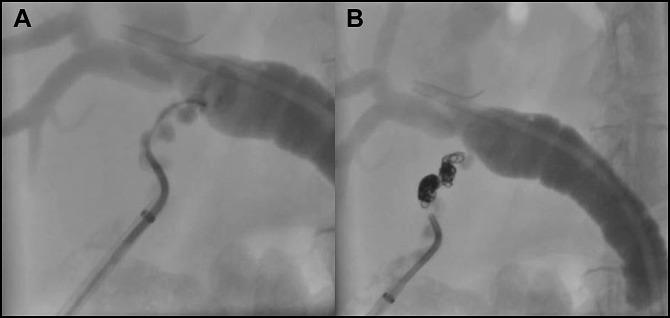

Cystic duct stump leak remains a difficult clinical problem despite advancements in endoscopic techniques. When these minimally invasive strategies fail, patients are often subject to high morbidity and mortality associated with open surgical exploration. We report the successful treatment of persistent biliary leak from the cystic duct stump following cholecystectomy using percutaneous transabdominal access of the cystic duct and coil embolization.

尽管内镜技术有所进步,但胆囊管残端漏仍是一个棘手的临床问题。当这些微创策略失败时,患者往往面临与开放手术探查相关的高发病率和死亡率。我们报告了经皮经腹进入胆囊管并进行线圈栓塞术成功治疗胆囊切除术后胆囊管残端持续性胆漏的病例。